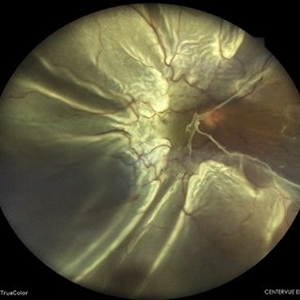

Giant Retinal Tear with Retina Detachment, Both Eyes

Fundus photograph of a 13 year-old female with giant retinal tear and retinal detachment in both eyes.

Photographer: Dr. Akansha Sharma-Retina Foundation, Ahmedabad

Condition/keywords: giant retinal tear, proliferative vitreoretinopathy (PVR)